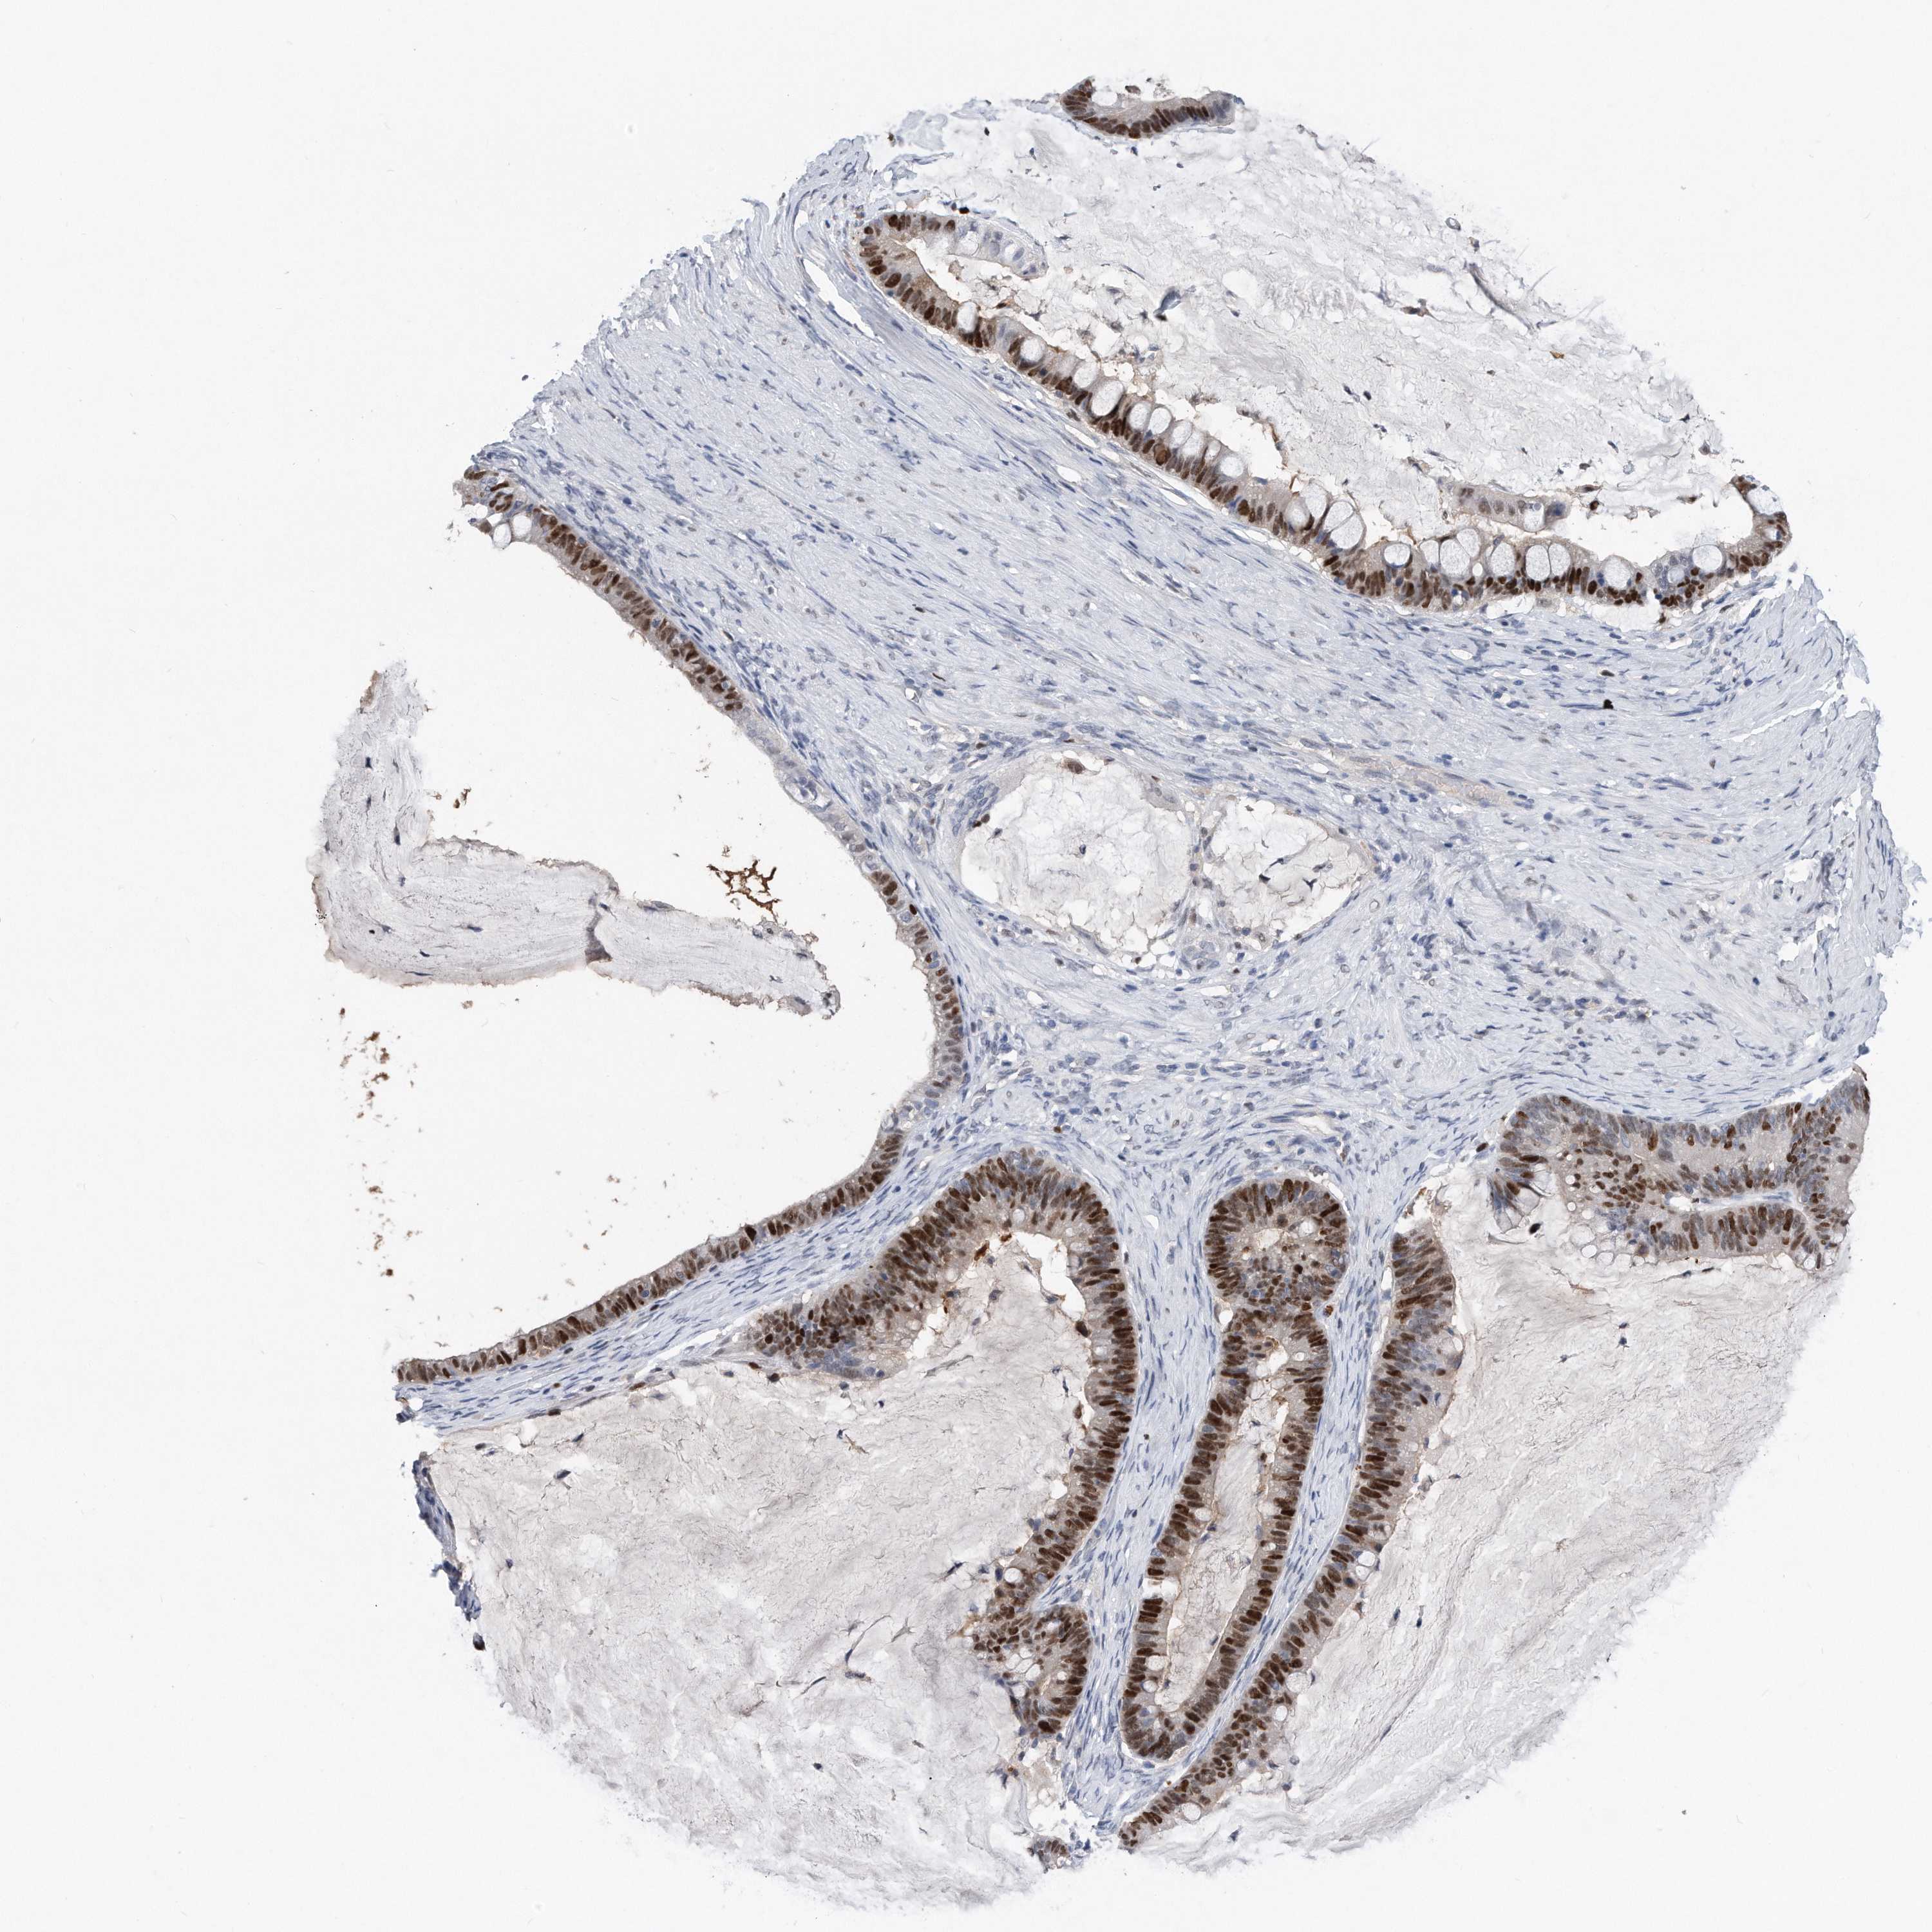

OVARIAN CANCER - Protein expressioni

A mouse-over function shows sample information and annotation data. Click on an image to view it in a full screen mode. Samples can be filtered based on level of antibody staining by selecting one or several of the following categories: high, medium, low and not detected. The assay and annotation is described here.

Note that samples used for immunohistochemistry by the Human Protein Atlas do not correspond to samples in the TCGA dataset.

Antibody stainingi

Antibody staining in the annotated cell types in the current human tissue is reported as not detected, low, medium, or high, based on conventional immunohistochemistry profiling in selected tissues. This score is based on the combination of the staining intensity and fraction of stained cells.

Each image is clickable and will lead to virtual microscopy that enables deeper exploration of all samples and also displays staining intensity scores, fraction scores and subcellular localization as well as patient and tissue information for each sample.

HPA030521

HPA030522

HPA030523

CAB000148

CAB080240

CAB080241

CAB080242

Staining

High

Medium

Low

Not detected

Intensity

Strong

Moderate

Weak

Negative

Quantity

>75%

75%-25%

<25%

None

Location

Nuclear

Cytoplasmic/membranous

Cytoplasmic/membranous,nuclear

Cystadenocarcinoma, serous, NOS

Carcinoma, endometroid

Cystadenocarcinoma, mucinous, NOS

Carcinoma, NOS